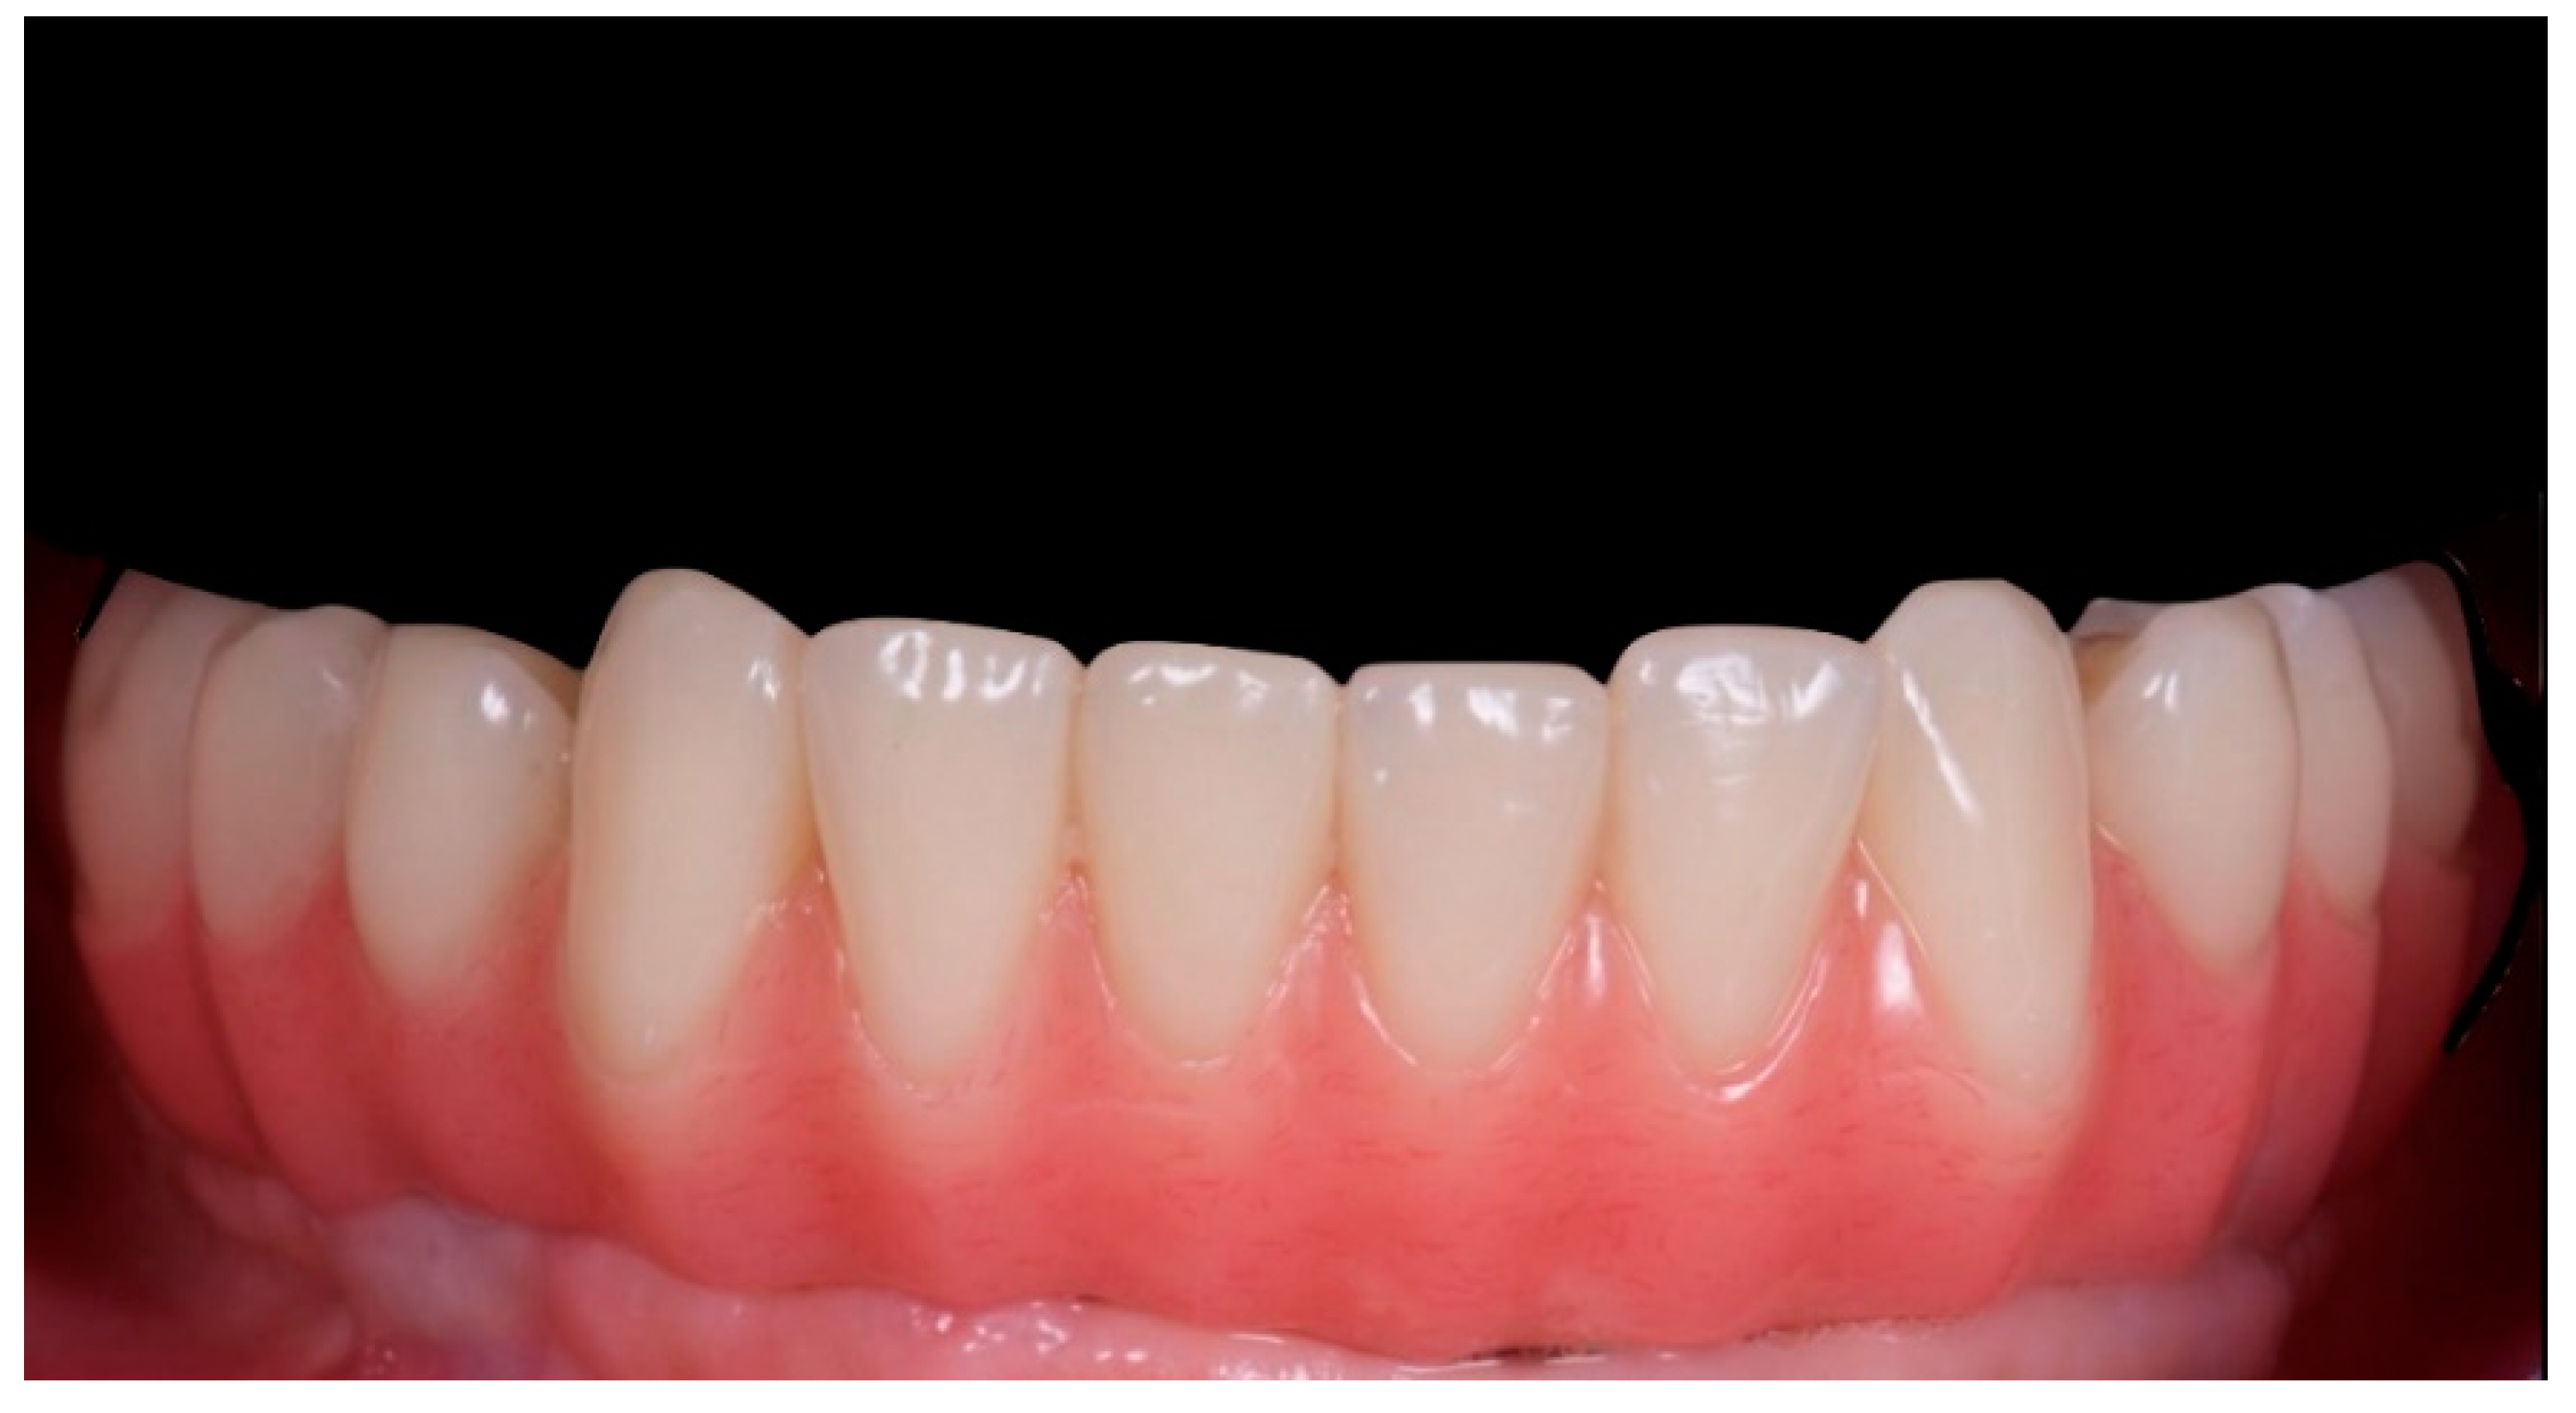

2. Materials and Methods